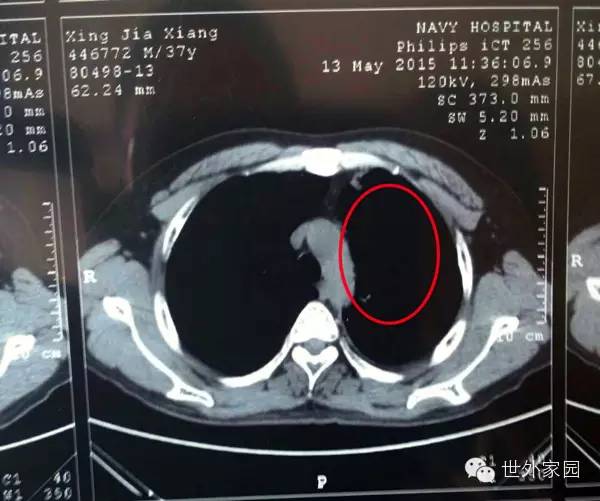

2014年12月17日肿瘤在CT上的显现(被圈部分)

2014年12月17日CT结果是肿瘤大小7.1*3.5cm

2015年5月13日复查CT肿瘤消失

肿瘤全部消失。(只剩少许胸腔积液,可以随时吸收掉;陈旧性病变是指曾经得肺结核自愈后留下的疤痕。)